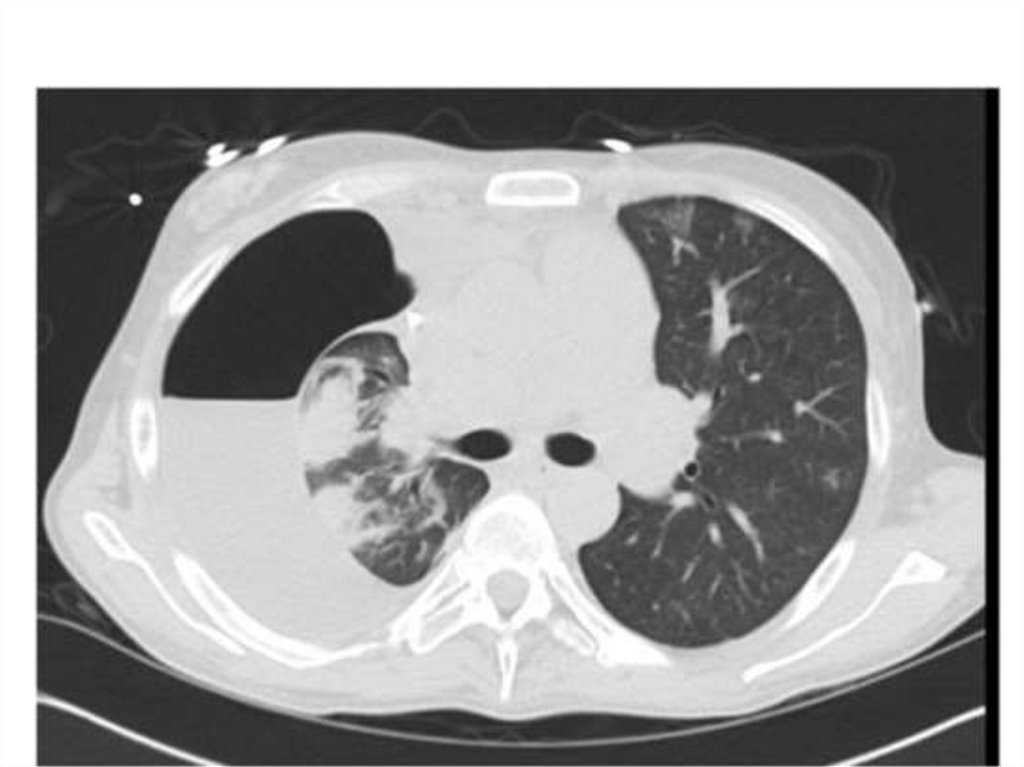

Пневмония